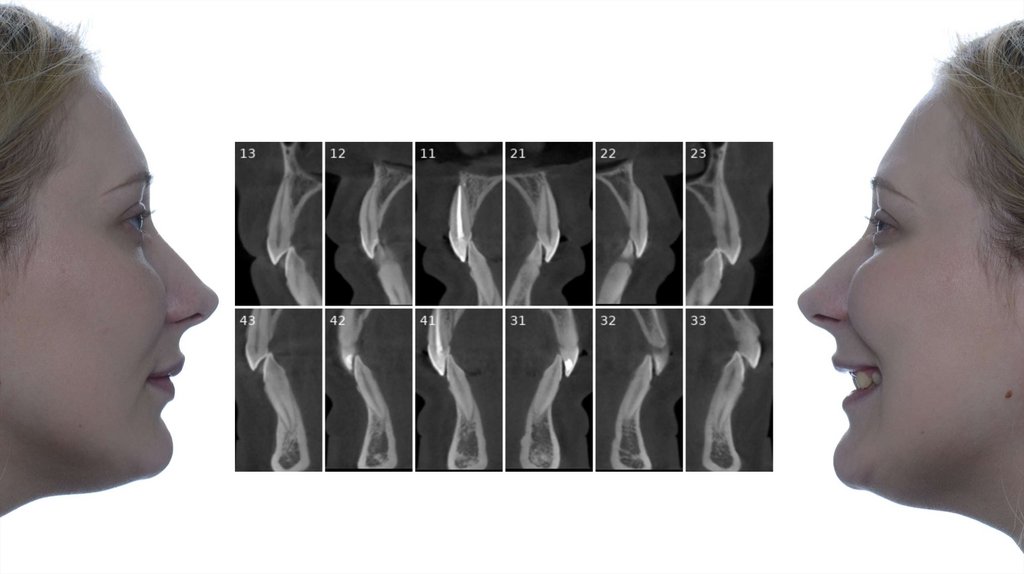

ДМ= 2 мм

ДМ= 4.1 мм

ДМ= 2.3 мм

ДМ= 2.2 мм